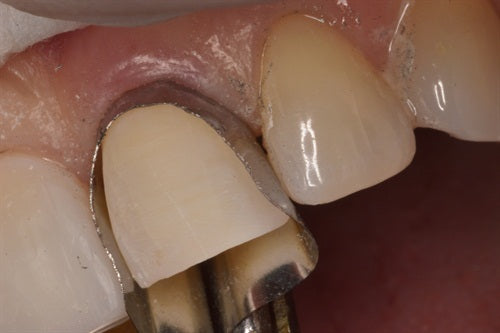

Margin Elevation by Clint K. Taura, DDS

Introduction: This case by Clint Taura, DDS is a wonderful example of how a sectional matrix secured inside a Greater Curve band can provide an excellent subgingival seal and isolation.... Read More